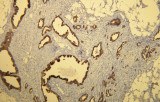

CE/IVD primary antibodies for GI pathology are optimized for routine diagnostic use, with the following attributes:

- Regulatory compliance ensures reproducibility across laboratories, with standardized protocols for FFPE tissues.

- Compatibility with automated staining systems, reducing variability in high-throughput diagnostic workflows.

By integrating CE/IVD primary antibodies into immunohistochemistry workflows, laboratories can achieve standardized, reproducible, and diagnostically meaningful results for gastrointestinal pathology.